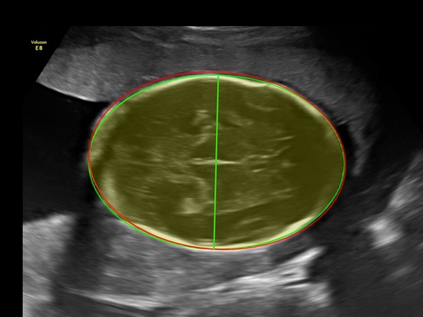

In this paper, we propose an end-to-end multi-task neural network called FetalNet with an attention mechanism and stacked module for spatio-temporal fetal ultrasound scan video analysis. Fetal biometric measurement is a standard examination during pregnancy used for the fetus growth monitoring and estimation of gestational age and fetal weight. The main goal in fetal ultrasound scan video analysis is to find proper standard planes to measure the fetal head, abdomen and femur. Due to natural high speckle noise and shadows in ultrasound data, medical expertise and sonographic experience are required to find the appropriate acquisition plane and perform accurate measurements of the fetus. In addition, existing computer-aided methods for fetal US biometric measurement address only one single image frame without considering temporal features. To address these shortcomings, we propose an end-to-end multi-task neural network for spatio-temporal ultrasound scan video analysis to simultaneously localize, classify and measure the fetal body parts. We propose a new encoder-decoder segmentation architecture that incorporates a classification branch. Additionally, we employ an attention mechanism with a stacked module to learn salient maps to suppress irrelevant US regions and efficient scan plane localization. We trained on the fetal ultrasound video comes from routine examinations of 700 different patients. Our method called FetalNet outperforms existing state-of-the-art methods in both classification and segmentation in fetal ultrasound video recordings.